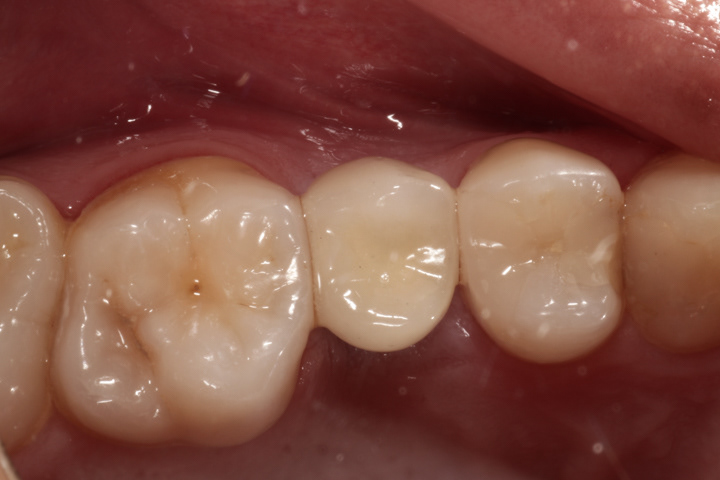

Alternatywą dla mostów są implanty, które pozwalają uzyskać całkowicie nowy ząb bez ingerencji w zęby sąsiednie. Mogą być zatem czyszczone nitką po obu stronach, lepiej prezentują się w strefach estetycznych. Ich wady to wyższa cena, dłuższy czas leczenia i wrażliwość na niedostateczną higienizację. Poniżej zamieszczam kilka przykładów wstawiania zębów za pomocą implantów.

Jest to standardowa procedura wszczepiania implantu i jego odbudowy ze wszystkimi etapami pośrednimi począwszy od usunięcia zęba do cementowanej korony.